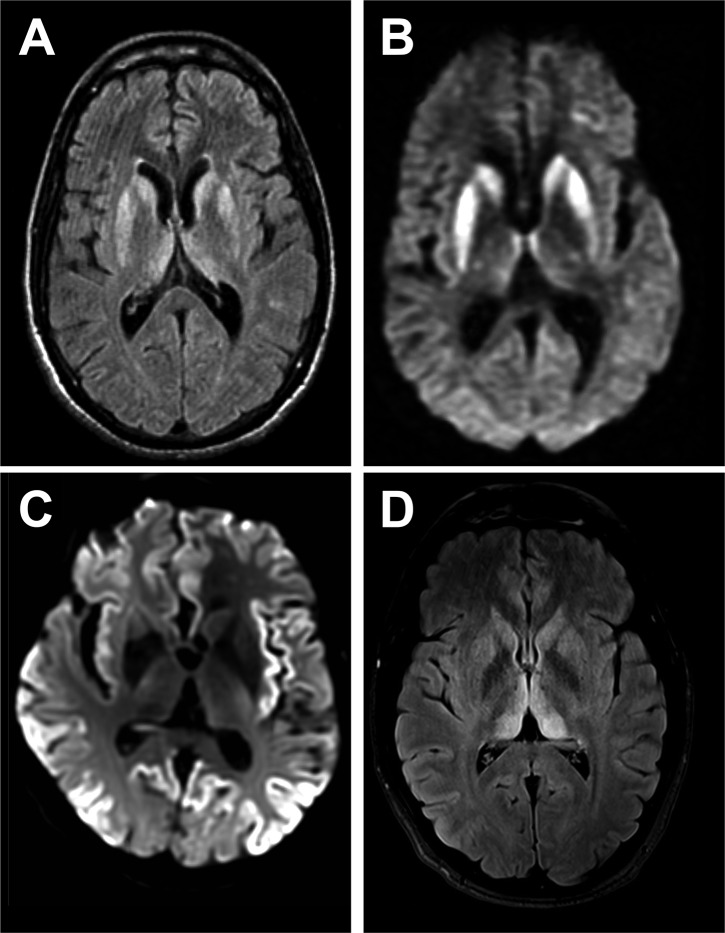

Prof. Dr. Ertuğrul, hastalığın prion adı verilen anormal proteinlerin beyinde birikmesiyle oluştuğunu, bu durumun beyin dokusunun süngerimsi hale gelmesine (BSE) yol açtığını belirtti.

“Deli dana hastalığı” veya bilimsel adıyla Bovine Spongiform Encephalopathy (BSE), ilk olarak sığırlarda görülen ölümcül bir beyin hastalığıdır.

İnsanlarda görülen formu variant Creutzfeldt-Jakob hastalığı (vCJD) olarak adlandırılır.